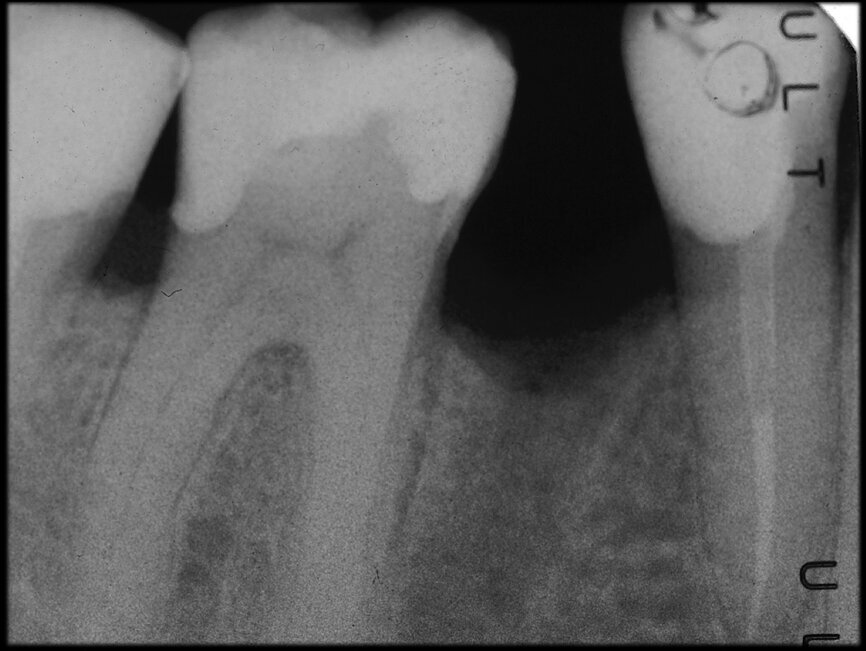

The case with which I would like to start my clinical review is a perfect example of how difficult it is to establish the origin of the patient’s symptoms on the basis of an intraoral radiograph alone. Not only does the 2D study fail to establish with certainty the presence of a lesion, but more importantly, it is impossible to establish the size, morphology and type of the lesion. An analysis of the 3D imaging, however, provides a clear picture of the clinical situation: the coronal and sagittal slices revealed the presence of a large lesion extending from the apex of the mesial root of this molar to the furcation, while the axial slices allow us to conduct a precise analysis of the endodontic anatomy and, in particular, the shape of the mesial root, which in this case was fused with the palatine root. A full overview of the case can, therefore, guide the decision-making process and direct the treatment plan towards a specific type of treatment (Figs. 1–4).